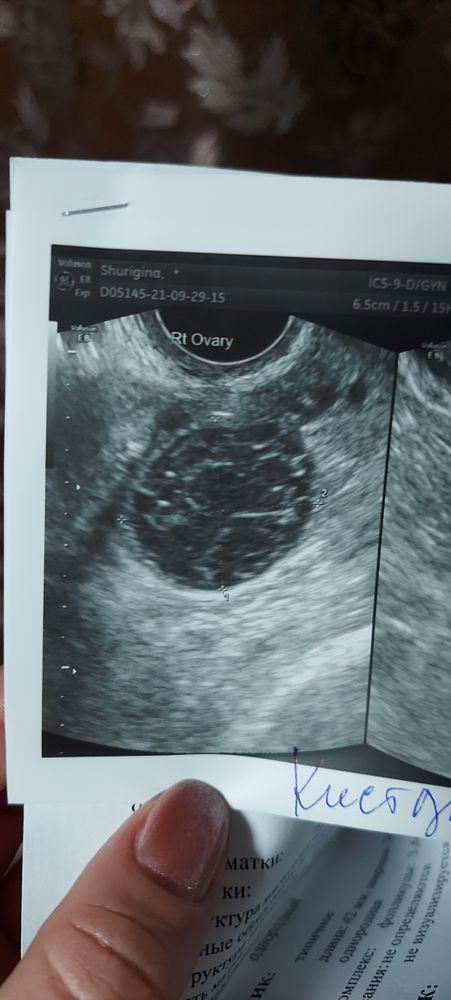

Всем здравствуйте. У меня спкя, была стимуляция клостом, + прогинова, на 10дц произошла овуляция, на 12 дц двухсторонние кисты жт, 1 жт с кровоизлияниеи. 35 и 32 мм, эндометрий 6,8мм.есть ли шанс на беременность?! Кто сталкивался с таким?! Врач сказала минимальный есть шанс.

Вот и у меня киста жт 28мм. И врач сказала,чтобы на беременность не рассчитывала.🥺

Кто-Я Для-Тебя, была стимуляция клостом с 5 по 9дц. На 11дц по узи дф не было. На 24дц пошла на узи из-за болей слева внизу живота,а там сбрприз-дф 22.5мм,29.09 на 29 дц уже киста жт 28мм. Не запрограммировала,просто слова въелись((

я с кистой жт забеременела, на 21 дц пришла, а там киста 32 мм. Тоже сказали, что скорее всего пролет, т.к. и эндоментрий был всего 8,5 мм. Но нет, все получилось. Киста меня еще в начале беременности заставила поволноваться, тк активно росла, в 7 недель была уже 62 мм. В 11 начала сдуваться.

У меня была лёгкая стимуляция пурегоном, факт овуляции подтверждён был на узи 1 мая, была киста жт около 35 мм вроде, эндометрий 7 мм. 8 мая уже полосатились тесты))